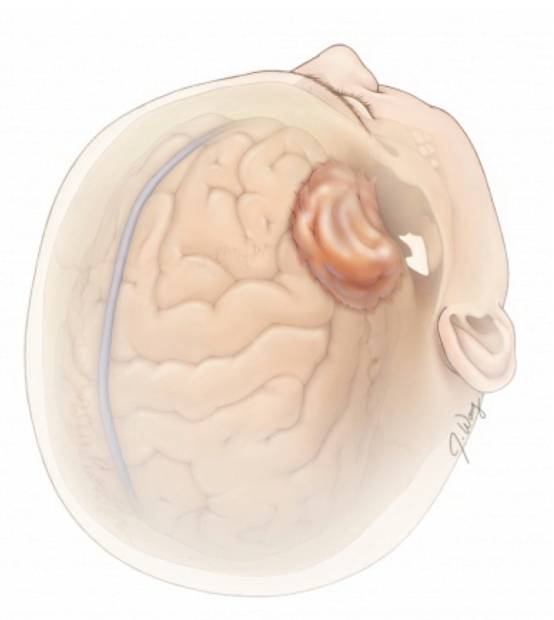

图2. 图示右侧外侧蝶骨嵴脑膜瘤及其与周围结构的关系。